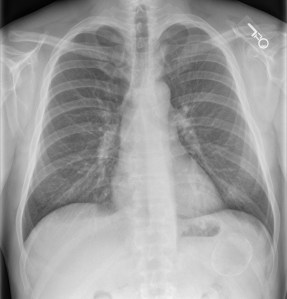

History: 50 year old male with chest pain and shortness of breath has an incidental finding.

The differential diagnosis for a calcified mass projecting over the left upper quadrant of the abdomen includes prior granulomatous disease such as histoplasmosis or tuberculosis, arterial calcifications such as a splenic artery aneurysm, splenic infarction, and splenic cyst. Less commonly, echinococcal (hydatid) cyst can present with a calcified mass; however, they are usually multiple. This patient’s diagnosis was a splenic cyst. Typically splenic cysts display eggshell calcifications. Splenic cysts can be either congenital or post-traumatic/post-infarction; however, this cannot be distinguished by imaging.